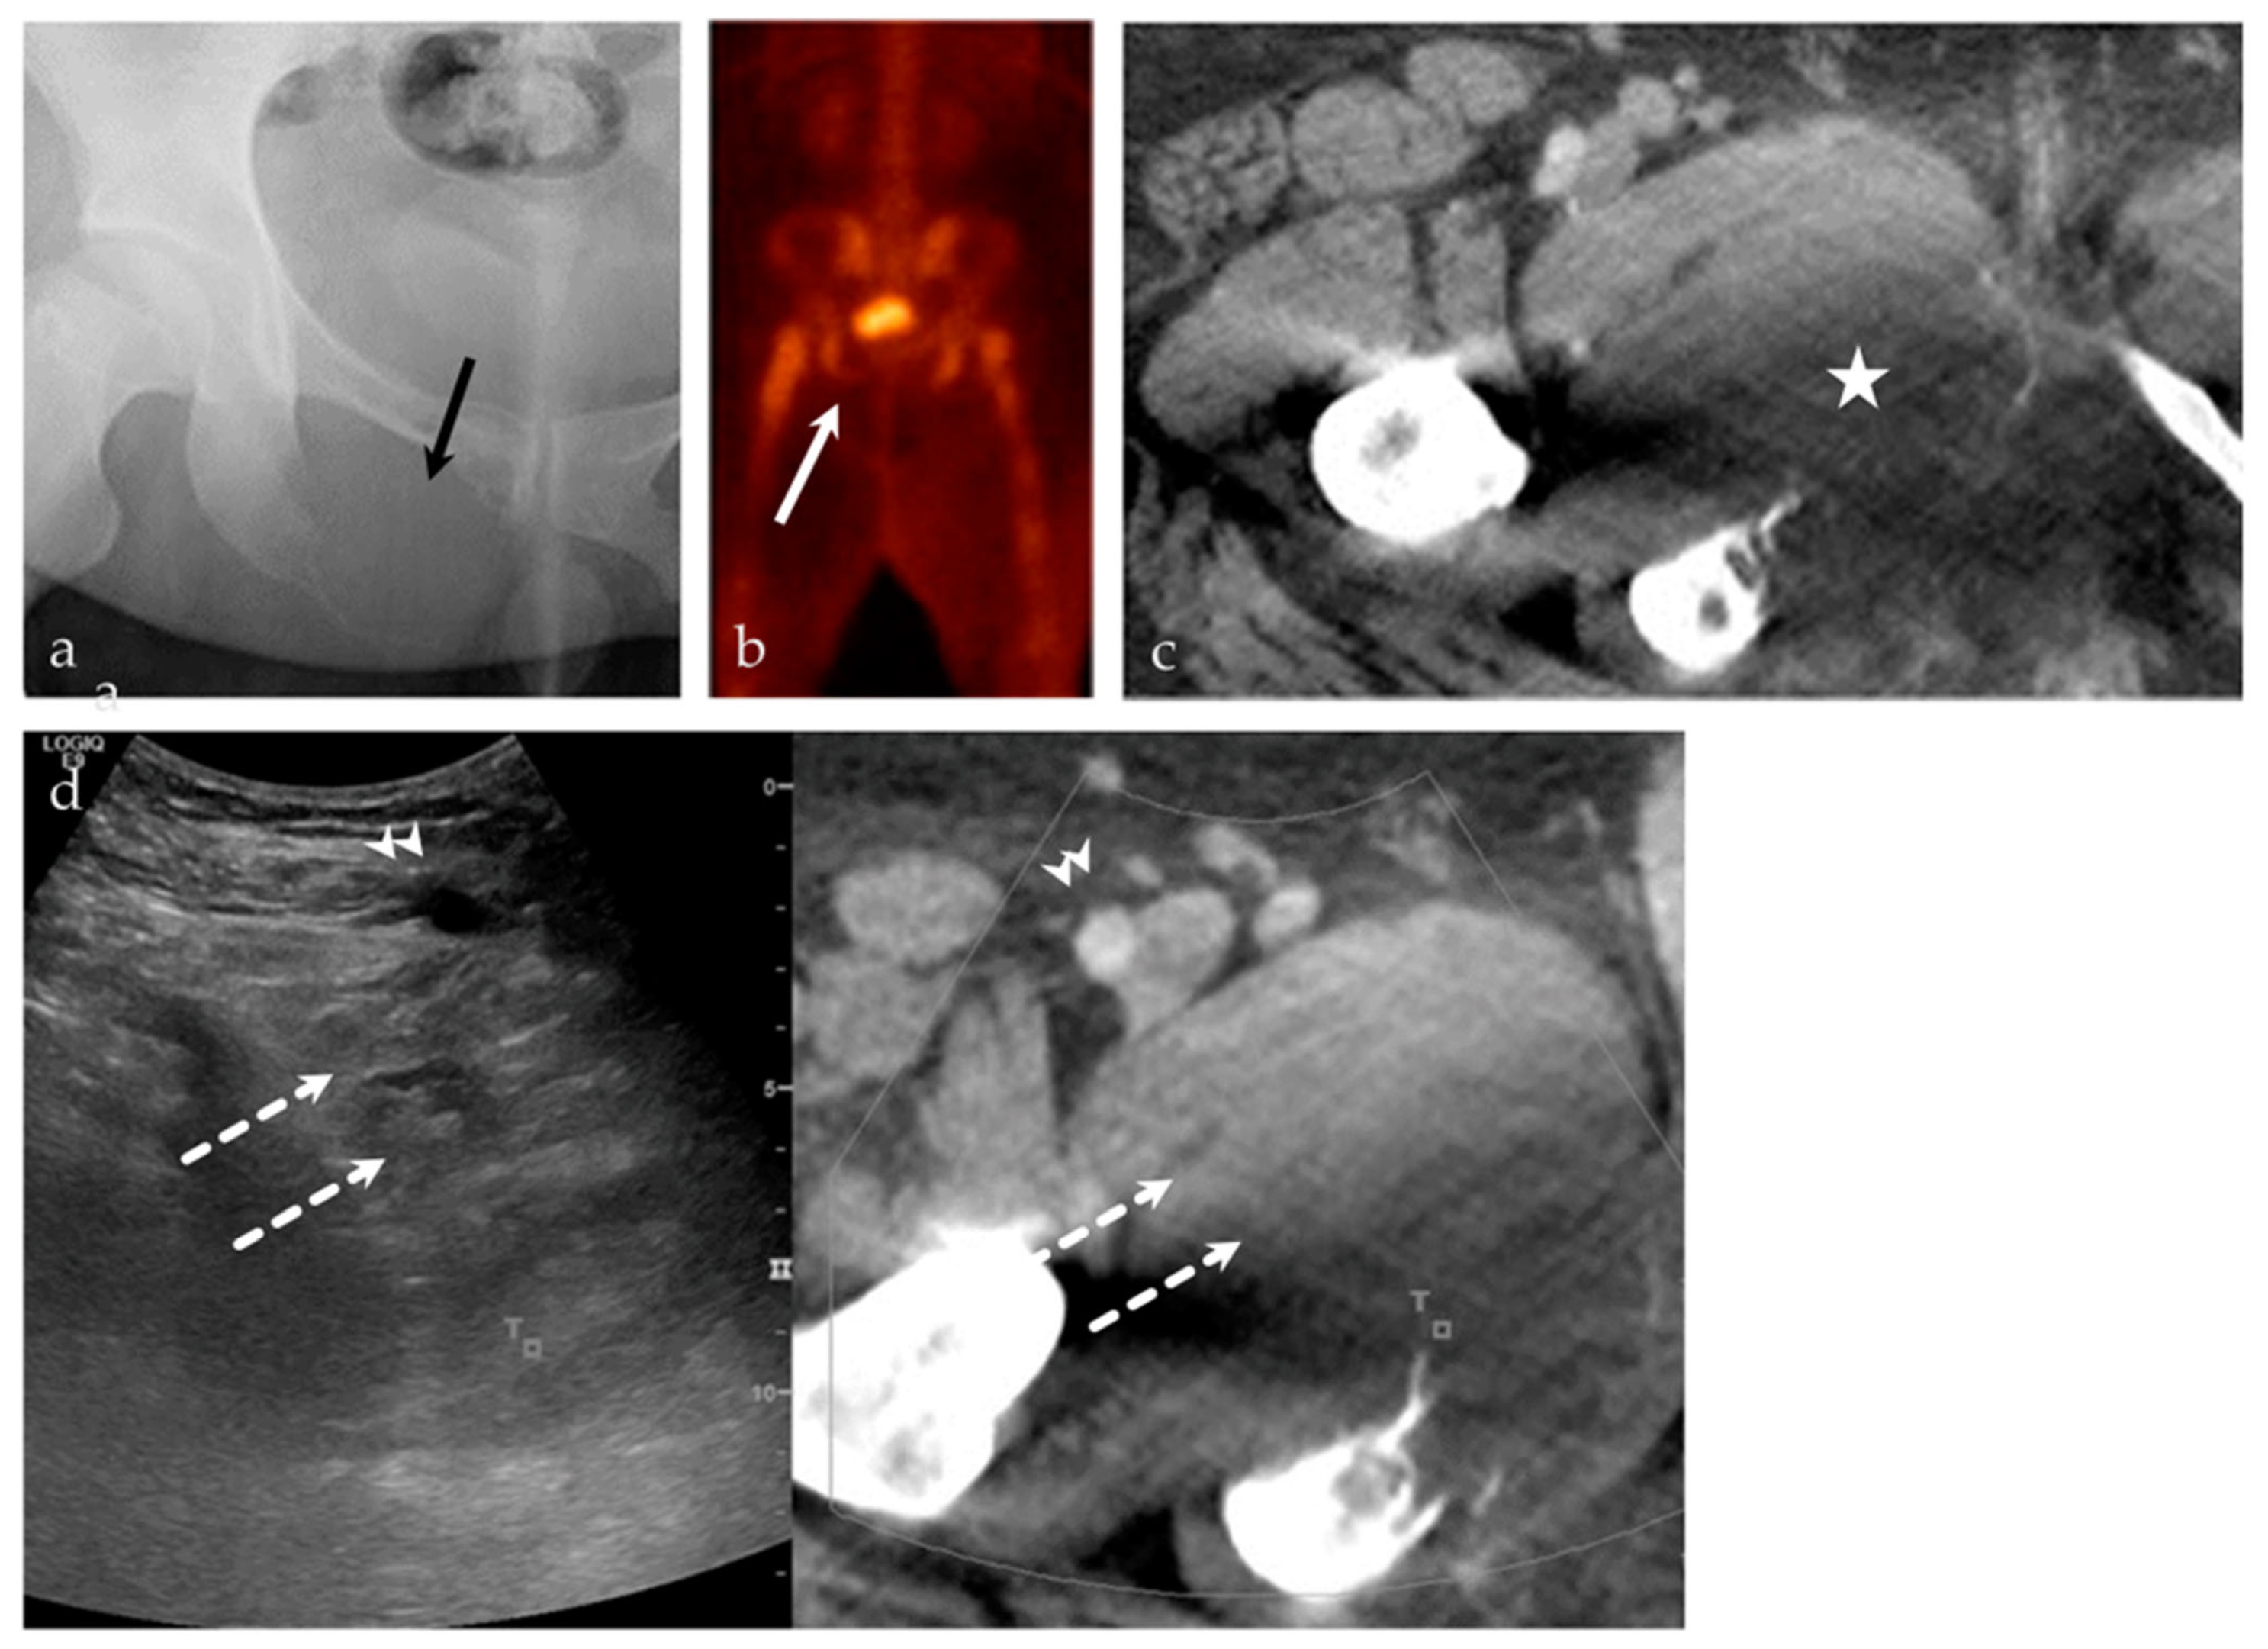

3.2.4. Targeted Percutaneous Lesion Biopsy and/or Aspiration

| 63/F | Left posterior iliac bone | US-PET | Metastatic disease, breast carcinoma | Neoplastic, malignant |

| 24/M | Right inferior pubic ramus | US-CT | Ewing sarcoma | Neoplastic, malignant |

| 93/M | Right femur | US-MRI | Metastatic disease, papillary thyroid carcinoma | Neoplastic, malignant |